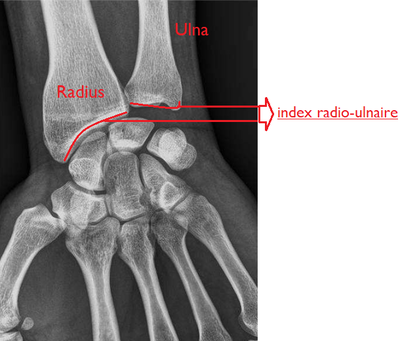

la partie médiale de l'articulation radio carpienne et la styloïde radial c est la même chose? l'index radio ulnaire c est entre styloïde radial et styloïde ulnaire ou la partie la plus basse de l'articulation radio carpienne et la styloïde ulnaire?

Pour l'index radio ulnaire, je vais demander confirmation au prof mais pour moi ce n'est pas la différence de longueur entre les styloïdes radiale et ulnaire, mais entre les faces inférieures du radius et de l'ulna (le radius étant plus bas).

index radio ulnaire.png